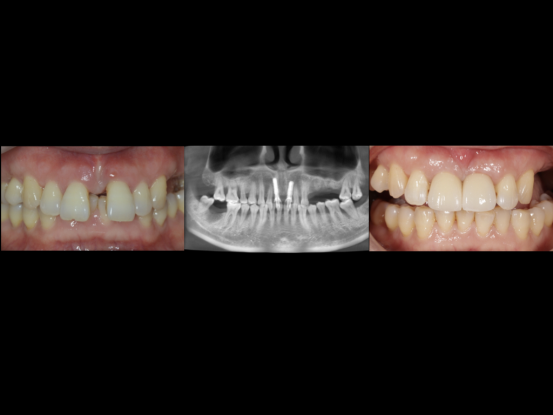

前牙美学区种植修复